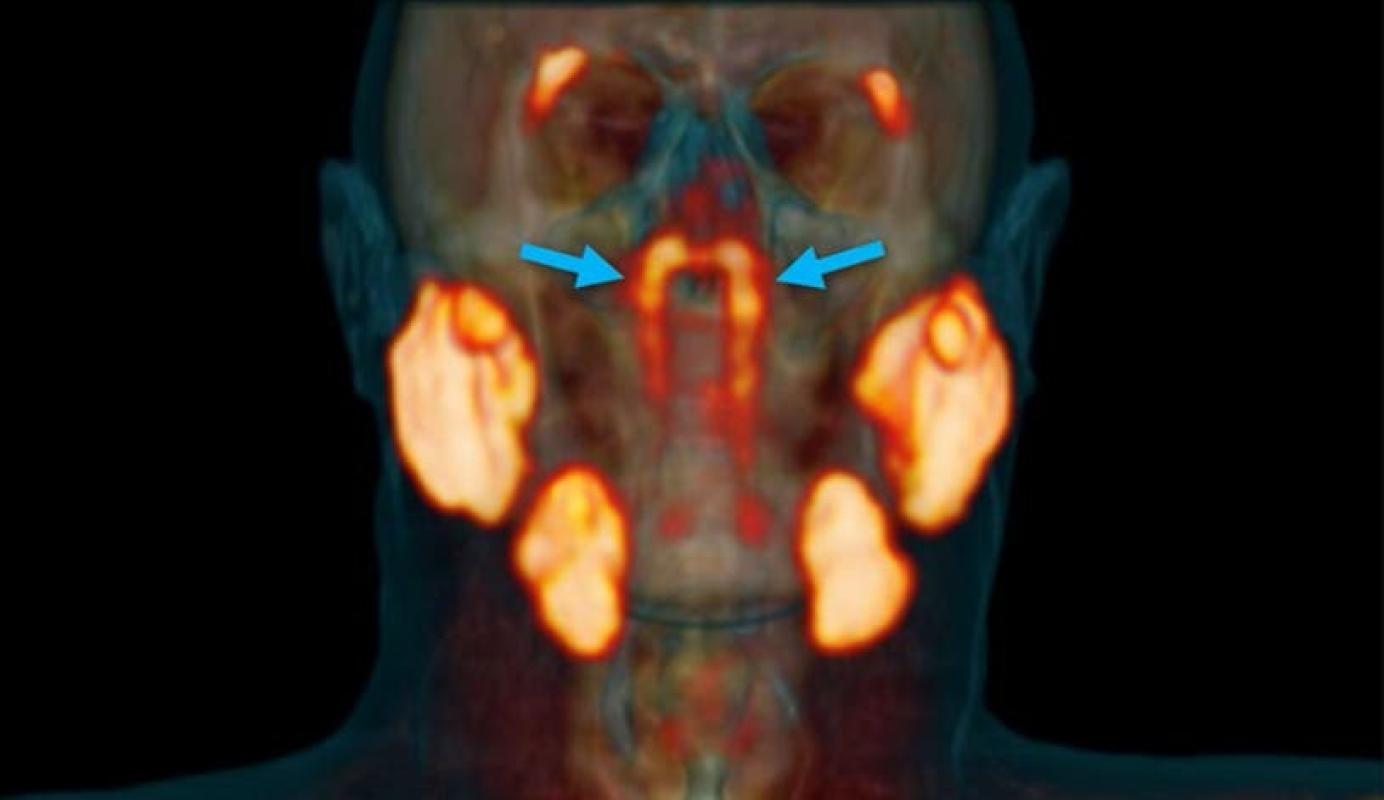

Sin embargo, en esta ocasión mostró algo completamente diferente ubicado en la parte posterior de la nasofaringe. “Por lo que sabíamos, las únicas glándulas salivales o mucosas de la nasofaringe son microscópicamente pequeñas y hasta 1.000 están distribuidas uniformemente por toda la mucosa”, dice Wouter Vogel del Instituto del Cáncer de los Países Bajos.

“Las dos nuevas áreas que se iluminaron resultaron tener otras características de las glándulas salivales”, dicen los autores. “Las llamamos glándulas tubarias, refiriéndonos a su ubicación anatómica [por encima del torus tubarius]”.

El nuevo descubrimiento realizado por el equipo de Vogel es mucho más grande y muestra un par de glándulas desconocidas. Aparentemente se trata de un cuarto conjunto de glándulas salivales principales, ubicadas detrás de la nariz y por encima del paladar, cerca del centro de la cabeza humana.